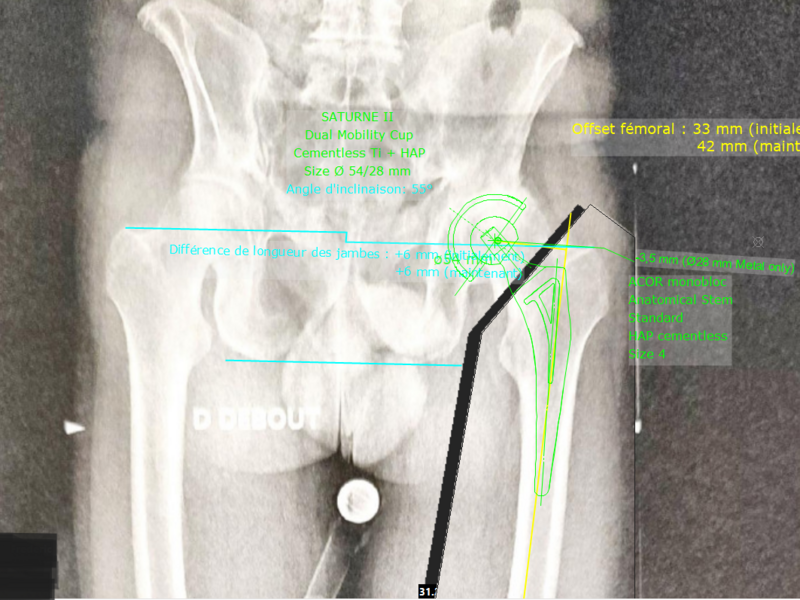

Album photo